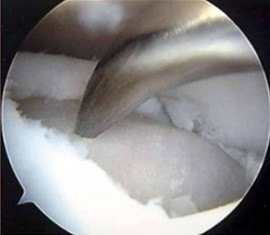

軟骨損傷が中程度の場合に行います。 大腿骨の非荷重部や反対側の膝関節から専用の器具を用いて円柱状に正常軟骨と軟骨下骨を一塊として採取し、軟骨損傷部に移植する治療法です。 ③自家培養軟骨移植術 比較的大きな軟骨欠損がある場合に行います。膝關節軟骨損傷常見問題 清除鬆脫的碎片或浮游的「游離體」 清除軟骨的碎片,使所有軟骨坑邊變得平滑乾淨(圖 4),同時清除在關節內的「游離體」,可顯著改善疼痛及 機械性能,即使乾淨了的軟骨坑洞不能治癒。這程序通常透過膝關節鏡進行。 微骨折術6/2/22 軟骨損傷とは 関節軟骨に、スポーツや交通事故等によって外力が加わり、軟骨組織が損傷し欠損することである。 関節軟骨は骨の表面に存在し、非常に滑らかであり、一定の弾力性を持っています。 このため、関節はスムーズに動くことができ、体重がかかっても衝撃を吸収することができます。 この軟骨組織が損傷したり欠損すると、スムーズに動く

軟骨損傷 北海道大学病院 スポーツ医学診療センター 軟骨は、膝関節や肘関節に代表される関節において関節内の骨の表面にある組織で、やや弾力性があり表面が非常に滑らかでほとんど摩擦がありません。 そのため、関節は痛みもなくスムーズに動くのです。 しかしながら、加齢や過大な負荷などによってこの軟骨組織が損傷を受けると、関節内で炎症が起こりと疑問の声が聞こえてきそうですね。 長引く膝の痛みの場合は高い確率で筋肉だけの問題ではなく、膝の関節の中の組織が損傷していると思われます。 (半月板や靭帯や軟骨など) 変形や損傷した組織を完全に元通りにする事は残念ながら出来ません。 しかし、痛みというのは色々な要素が複雑に絡み合っています。 膝の痛みで説明すれば、筋肉の過緊張、炎症